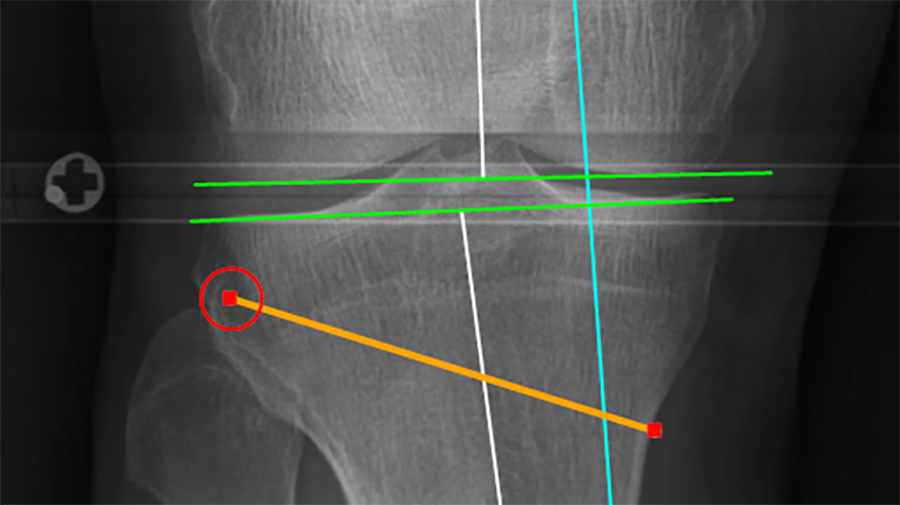

Introducing the new Distal Radius Intramedullary Nail (DRIM-Nail) for the fixation of extra-articular fractures

In response to various clinical complications following fixation of distal radius fractures using CRPP and ORIF techniques, a collaboration between the University of Balgrist, Disrad AG, the AO Technical Commission's Hand Expert Group, the AO's Development Incubator and 41medical has witnessed the design and development of an intramedullary implant for extra-articular distal radius fractures.